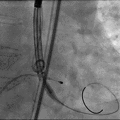

根部造影

导丝跨瓣

输送器定位

释放瓣膜

瓣膜释放完毕

术后造影及超声探查未见瓣周漏,跨瓣压差由术前85mmHg降为6mmHg,术中及术后未出现相关并发症,手术圆满完成。